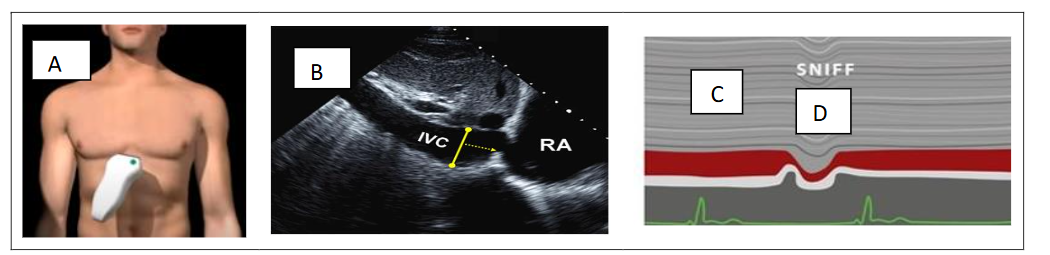

STEP 2 – DE ESTIMATION OF RIGHT ATRIAL PRESSURE (RAP)

An assumed RAP is routinely added to the TR to estimate the sPAP. RAP pressure estimation is based on inferior vena cava (IVC) diameter in the subcostal view during quiet respiration and after “sniff” maneuver. The subcostal view is most useful for imaging the IVC, with the IVC viewed in its long axis. The measurement of the IVC diameter should be made at end-expiration and just proximal to the junction of the hepatic veins that lie approximately 0.5 to 3.0 cm proximal to the ostium of the right atrium. To accurately assess IVC collapse, the change in diameter of the IVC with a sniff and also with quiet respiration should be measured, ensuring that the change in diameter does not reflect a translation of the IVC into another plane. The measurements are done at end-diastole (figure 2). IVC diameter ≤ 2.1 cm that collapses >50% with a sniff suggests a normal RAP of 3 mm Hg (range, 0–5 mmHg); IVC diameter > 2.1 cm that collapses <50% with a sniff suggests a high RAP of 15 mm Hg (range, 10–20 mmHg). In indeterminate cases in which the IVC diameter and collapse do not fit this paradigm, an intermediate value of 8 mm Hg (range, 5–10 mmHg) may be used.

Figure 2. RAP estimation based on inferior vena cava (IVC) diameter in the subcostal view (A-B) during quite respiration (C) and after “sniff” maneuver (D).